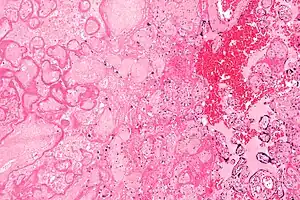

| Micrograph of a placental infarct (left of image), a cause of intrauterine hypoxia. H&E stain. | |

Intrauterine hypoxia (also known as fetal hypoxia) occurs when the fetus is deprived of an adequate supply of oxygen. It may be due to a variety of reasons such as prolapse or occlusion of the umbilical cord, placental infarction and maternal smoking. Intrauterine growth restriction may cause or be the result of hypoxia. Intrauterine hypoxia can cause cellular damage that occurs within the central nervous system (the brain and spinal cord). This results in an increased mortality rate, including an increased risk of sudden infant death syndrome (SIDS). Oxygen deprivation in the fetus and neonate have been implicated as either a primary or as a contributing risk factor in numerous neurological and neuropsychiatric disorders such as epilepsy, attention deficit hyperactivity disorder, eating disorders and cerebral palsy.[1][2][3][4][5][6]